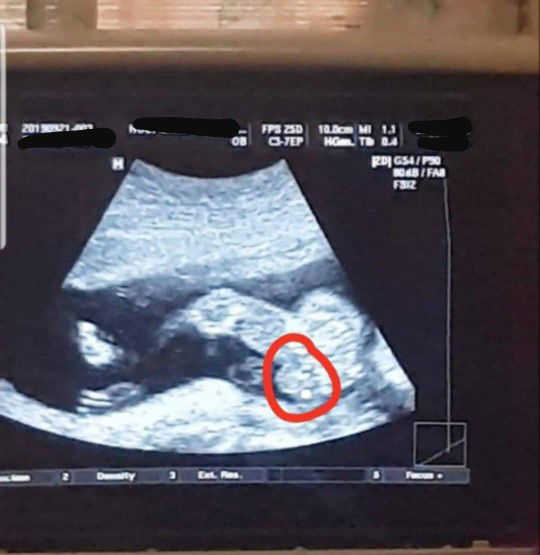

Ano po sa tingin niyo? ?

Hello mommies.. nag pa ultrasound ako kahapon kasi excited na ako.. pero hndi pa masabi ni ob kung boy o girl kasi matambok.. parang scrotum/ ball sac daw nakikita nya o pwedeng matambok lang ung pempem.. pero naisip ko naman masyado ata matambok kung pempem un ni baby kasi kung ikukumpara halos kasize na ng tuhod nya e.. kaya feeling ko tuloy boy sya at itlog nya ung nakaumbok na yan sa pic ? un nga lang hndi kita ung lawit, kaya confused ako baka girl nga siya. ? ano po sa tingin nyo? Hehe 19weeks po now si baby..i-ultrasound po ulit ako next month ? Thanks po.. ?